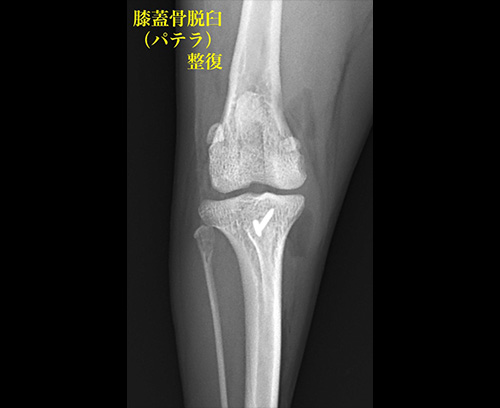

膝蓋骨(パテラ)脱臼

膝蓋骨(パテラ)内方脱臼

膝蓋骨脱臼